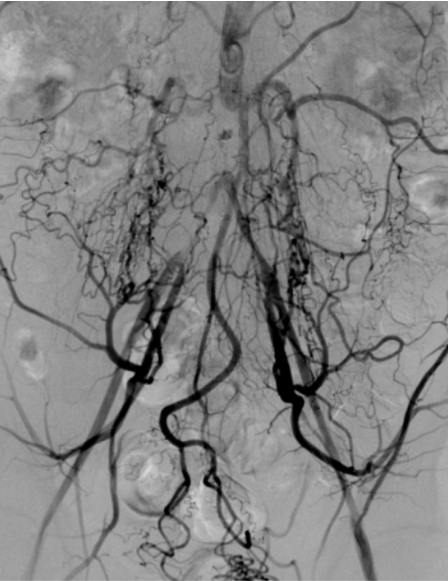

💡 How Balloon Angioplasty Works

Step 2: Procedure

A catheter with a balloon is guided into the blocked artery. The balloon inflates, expanding the artery and restoring blood flow.

Step 3: Restored Circulation

✔ Improved blood flow

✔ Reduced symptoms

✔ Better tissue health

(Sometimes a stent is placed to keep the artery open.)